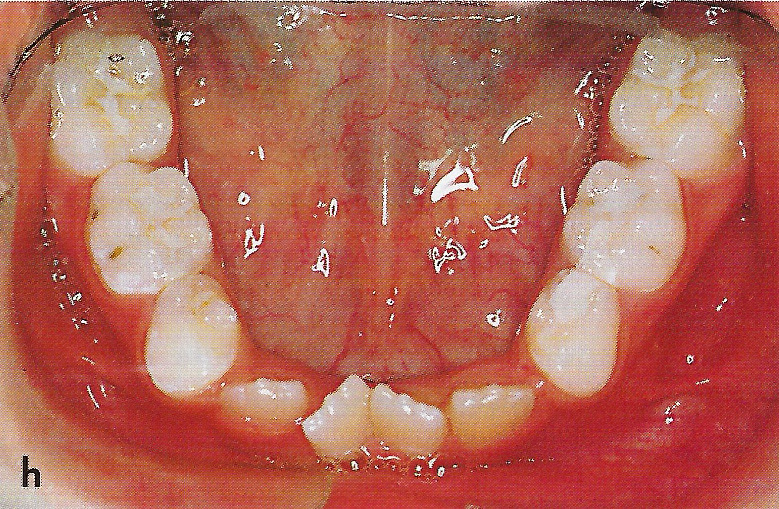

Abb. 1 a bis h Extra- und intraorale Ansicht der Patientin vor Behandlungsbeginn: Kopfbiß beziehungsweise umgekehrter Schneidezahnüberbiß und beidseitiger Kreuzbiß als Folge einer maxillären Hypoplasie sowie hälftenungleicher Mesialbiß infolge mandibulärer Verschiebung nach rechts.

• Ankylose Abb.1h

Diese Patientin war zu Behandlungsbeginn 7 Jahre alt. Sie hatte einen hälftenungleichen Mesialbiß infolge mandibulärer Verschiebung mit Kopfbiß beziehungsweise umgekehrter inzisaler Stufe, rechtsseitigem vollem Kreuzbiß und linksseitigem doppeltem Höckerbiß, maxillärer Kompression sowie Platzmangel in beiden Kiefern (Abb. 1 a bis h). Die kephalometrische Analyse ergab eine progene Kieferlagebeziehung, bedingt durch eine unterentwickelte Maxilla bei vertikalem Gesichtsschädelaufbau.